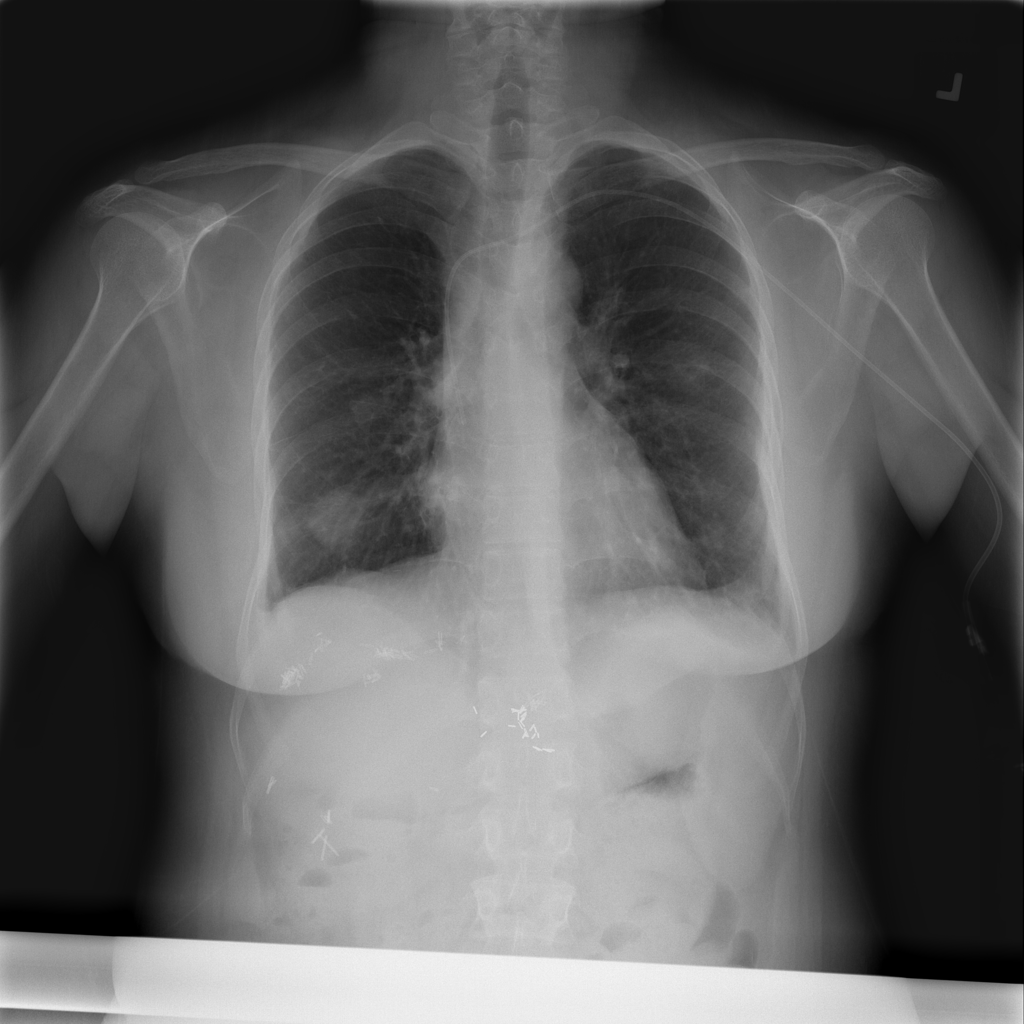

PAT-50E5 · IMG-000Nodule

PAT-50E5 · IMG-000

PA